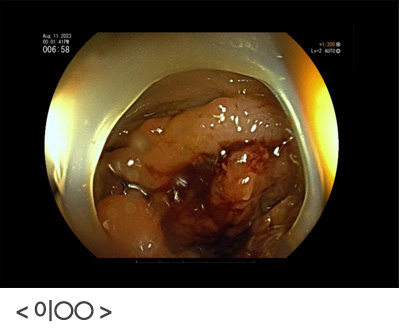

남자와 폐경 후 여성분들에게 나타나는 빈혈은 위장관의 악성질환에서 조금씩 피가 나는 것이 원인일수 있기 때문에, 반드시 위, 대장내시경을 시행하여 위암이나 대장암이 있는지 확인이 필요합니다. 만성질환에 동반된 빈혈은 환자분이 적응하면서 어지러운 증상을 호소하지 않기 때문에, 불편감을 못 느낄수도 있으나 그냥 지나치지 말고 반드시 내시경검사를 통하여 확인할 필요가 있다는 것을 다시 한번 깨달은 증례였습니다.